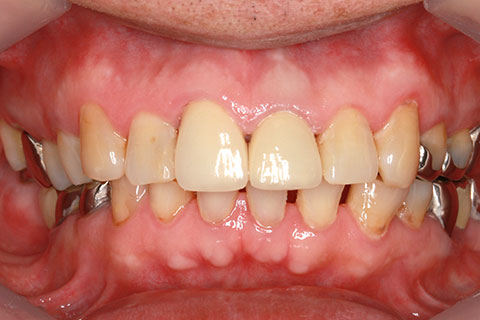

• オールセラミックの症例4

治療前

治療後

古くなった被せをジルコニアセラミックスで治療。

年齢・性別

65歳女性

治療期間

1ヶ月

抜歯

なし

治療費

35.2万円

備考

古くなった被せを新たなセラミックス冠にする。

治療内容

歯質を削除し、セラミック冠をセメント合着

施術の副作用(リスク)

知覚過敏、歯髄炎、荷重負担